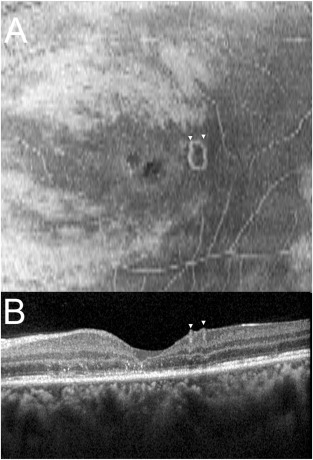

ILM处分割的Enface OCT(海德堡光谱HRA+OCT)显示ILM顶部的线虫处于盘绕位置(图3A),在相应的横向SD-OCT图像中不完全可见(图3B)。

图3:(A)在ILM处分割的Enface OCT(海德堡光谱),显示ILM顶部盘绕的线虫(箭头);(B) 相应的横向SD-OCT图像。